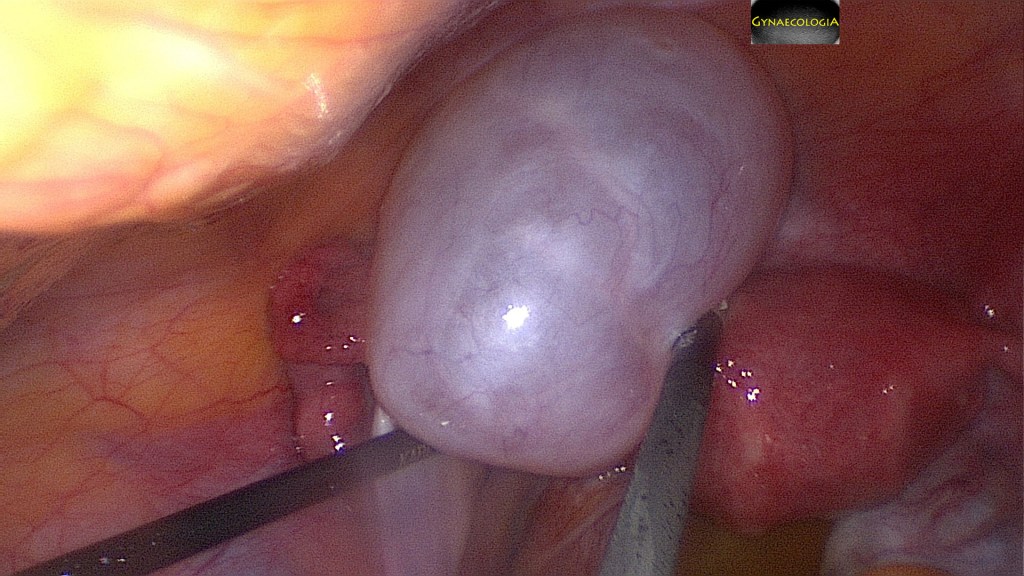

Treatment of a mucinous cystadenoma is surgical.

Removal of the cyst alone has a high risk of recurrence.

Spillage of the contents of the cyst should be avoided.

The intact removal of the ovary is suggested. This may be achieved either by laparotomy or laparoscopy. In the absence of malignancy and/or pseudomyxoma peritonei the mere inspection of the normal appendix suffices (Brown, J., & Frumovitz, M., 2014).